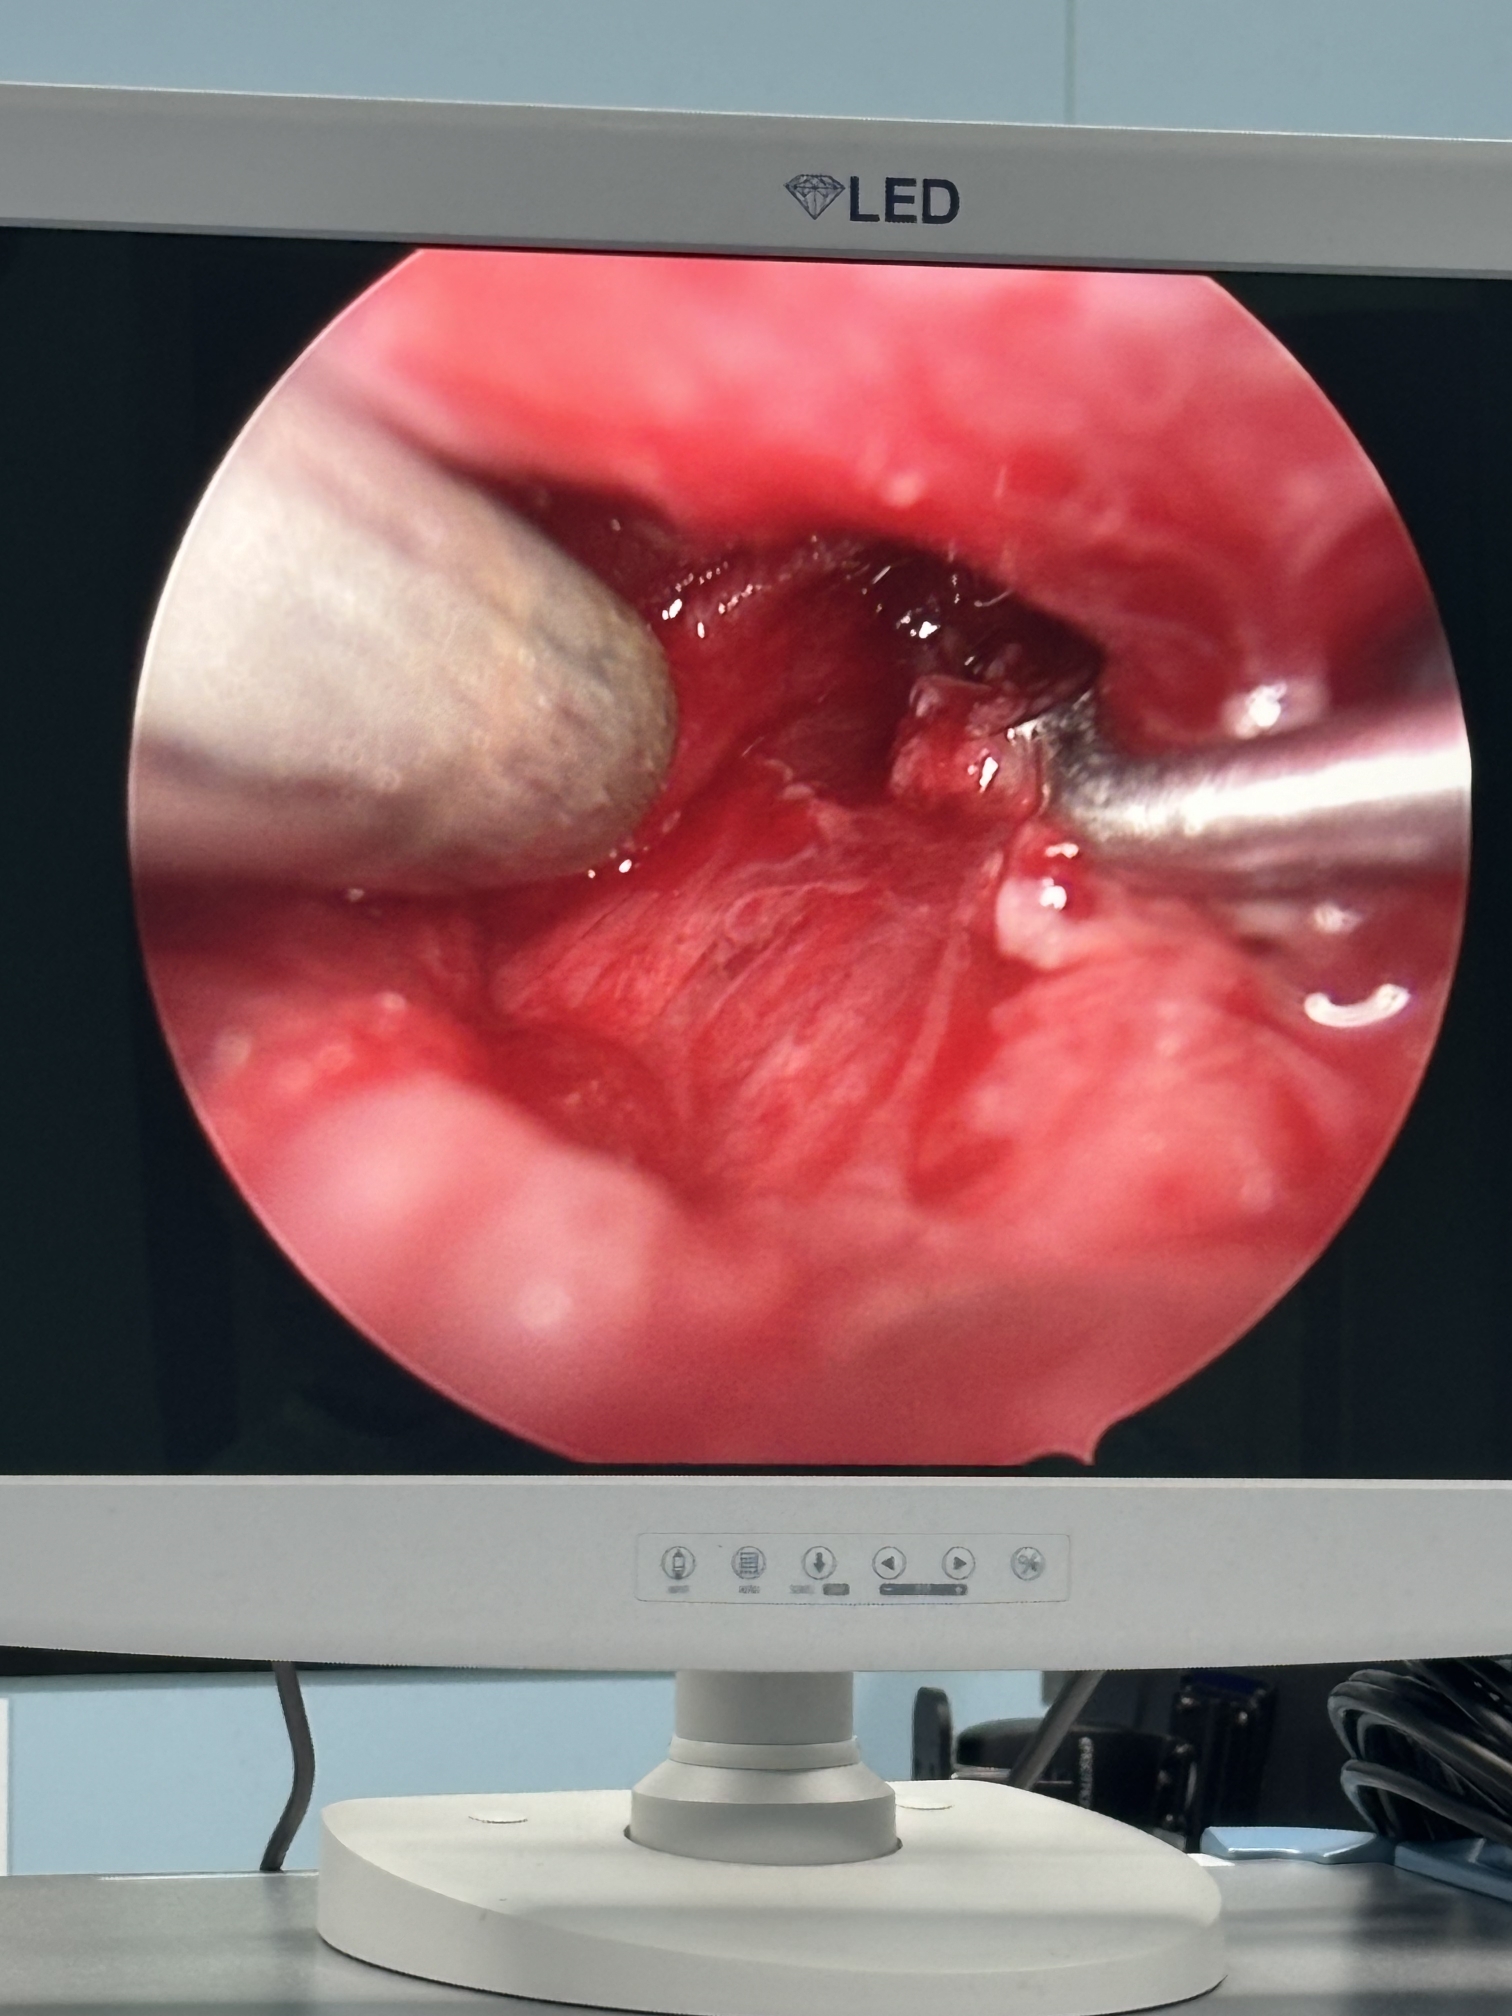

膝关节疼痛,原因是椎管内肿瘤,哑铃型生长,全切肿瘤,保留神经,疼痛症状消失…